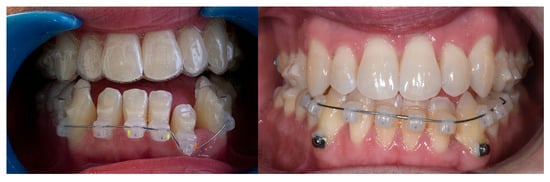

2.3. Treatment Progress

Treatment began with the extraction of the upper right second molar, performed by the referring general dentist. Once the Carriere® Motion appliances were bonded from the lower right first premolar to the lower right second molar and from the lower left first premolar to the lower left first molar, and the maxillary Invisalign® aligners were in place, the first phase of Class III intermaxillary elastics was initiated using ¼″, 6 oz elastics for one month, then intensified with 3/16″, 8 oz elastics (Figure 2). Achievement of a bilateral Class I molar relationship marked the transition to the second phase of treatment (Figure 3).

Figure 2. Intraoral view of the Carriere® Motion 3D Class III appliance during the sagittal correction phase.

Figure 3. Evolution of treatment after the use of the Carriere appliance with Sagittal First philosophy.